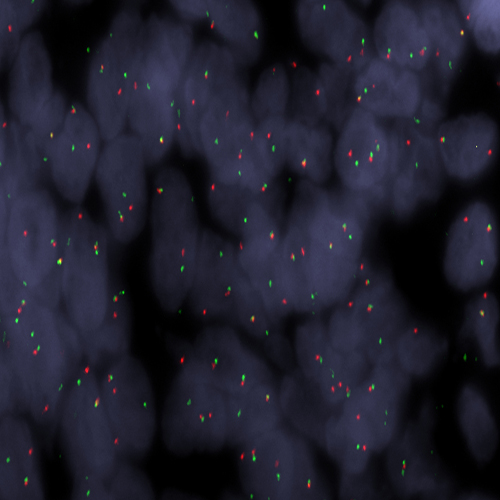

Human tonsil: immunohistochemical staining for CD10. Note membrane staining of germinal centre B cells. CD10: clone 56C6

CD10 antigen, also called neprilysin, is a 100 kD cell surface metalloendopeptidase which inactivates a variety of biologically active peptides. It was initially identified as the common acute lymphoblastic leukemia antigen (CALLA) and was thought to be tumor-specific. Subsequent studies, however, have shown that CD10 antigen is expressed on the surface of a wide variety of normal and neoplastic cells. In other lymphoid malignancies, CD10 antigen is reported to be expressed on cells of lymphoblastic, Burkitt's and follicular lymphomas. CD10 antigen has been identified on the surface of normal early lymphoid progenitor cells, immature B cells within adult bone marrow and germinal center B cells within lymphoid tissue. It is also expressed in various non-lymphoid cells and tissues, such as breast myoepithelial cells, bile canaliculi, fibroblasts, with especially high expression on the brush border of kidney and gut epithelial cells. (G. McIntosh et al. American Journal of Pathology. 154(1): 77-82 (1999)).